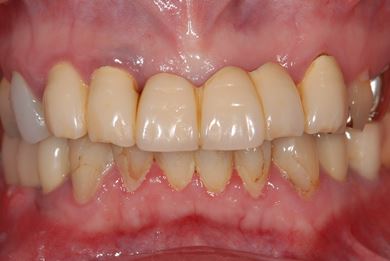

インプラントの症例写真 IMPLANT

骨再生インプラント治療

| 治療方針 | 右下奥、骨再生法によりインプラント治療を可能にする。 | ||||||||||||||||||||||||||||||||

| 治療内容 | インプラント3本(GBR、テンポラリーインプラント+仮歯)、ハイブリッドセラミックブリッジ3本、ハイブリッドセラミッククラウン2本 | ||||||||||||||||||||||||||||||||